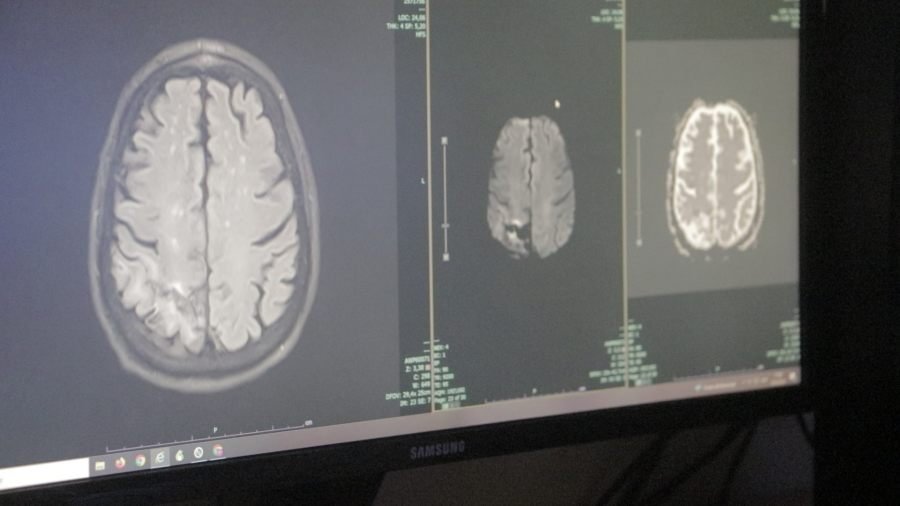

El Dr. Christian Bortoluzzi, del Servicio de Neurología del Hospital Escuela de Agudos Dr. Ramón Madariaga explicó que el ACV o Accidente Cerebro Vascular es una emergencia médica que se produce por la interrupción del flujo sanguíneo cerebral.

“Existen dos grandes tipos, uno es el isquémico que se produce por la oclusión de una arteria y el otro es el hemorrágico que se produce por la ruptura de una arteria.

En ambos se produce la muerte neuronal”, sostuvo el profesional.